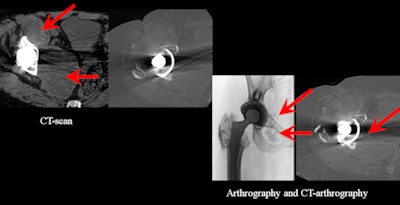

![]() |

| A 55-year-old female patient with a large pelvic collection recurring after drainage, suspected to be related to the hip prosthesis. No infection, no metal, but presence of histamine in the collection. CT arthrography demonstrates the communication between the joint and the collection. (Provided by Prof. Alain Blum) |